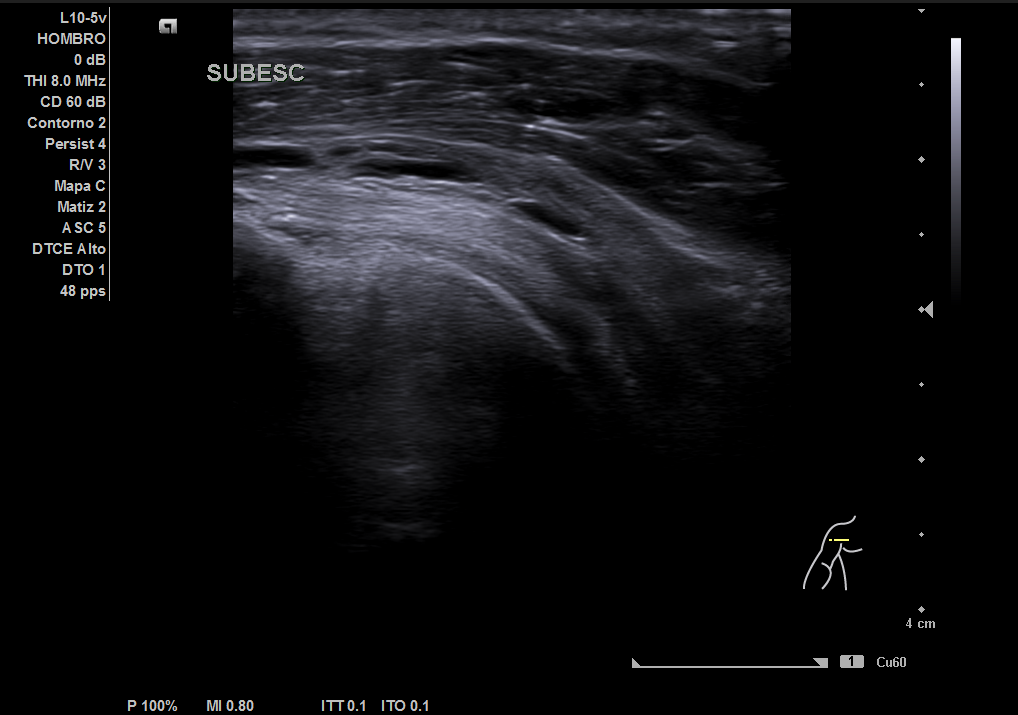

Descripción de los hallazgos ecográficos y las imágenes más relevantes para la resolución del caso

En la ecografía realizada observamos una rotura completa del tendón supraespino, rotura parcial del subescapular y severo derrame peritendón del bíceps junto con derrame articular glenohumeral.